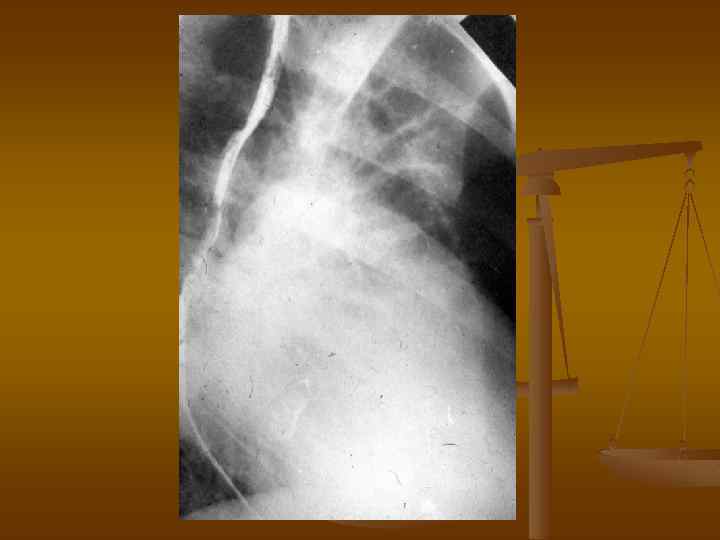

Рентгенограмма грудной клетки больного со стенозом трехстворчатого клапана во второй косой проекции.